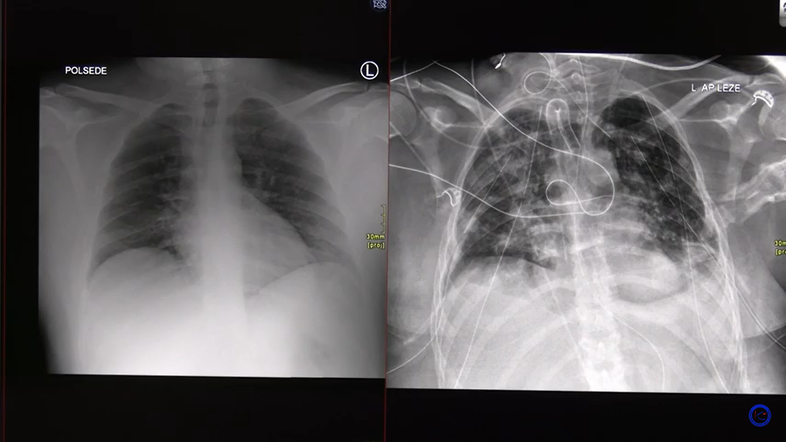

Rentgenska slika pljuč Youtube/prtscr

Dva primera covid pljučnice - pri enem bolniku se je stanje relativno hitro izboljšalo, drugemu, le 30-letnemu bolniku, pa so morali presaditi pljuča.

Zdravnik Matjaž Turel je s pomočjo rentgenskih in CT posnetkov predstavil dva primera potekov covid pljučnice. Kot je pojasnil, se pri 90 odstotkih bolnikov pljuča lepo popravijo. A vseeno se lahko zaplete.

Pri prvem bolniku na rentgenski sliki sprva ni bilo videti kakšnih velikih sprememb, le nekaj meglic. Le štiri dni po tem pa je prišlo do poslabšanju stanja. Bolnik je prejemal kisik, a so se meglice začele gostiti, po obeh pljučnih krilih so se pojavili madeži, ki so dva dni kasneje postali še bolj gosti. V pljučih se je razplamtelo vnetje, ki ga je povzročil koronavirus, je pojasnil Turel. Stanje se je k sreči stabiliziralo, bolnik je potreboval le kisik, respiratorja pa ne. Stanje se je nato izboljšalo, zato je bil bolnik odpuščen v domačo oskrbo.

Mesec po prihodu v bolnišnico je bilo na CT-ju videti še nekaj sprememb in brazgotin, a se je stanje izboljšalo, je povedal zdravnik. "Lani smo mislili, da bo veliko brazgotin ostalo, vendar posnetek po zadnji kontroli v oktobru kaže, da so skoraj vse spremembe izginile."